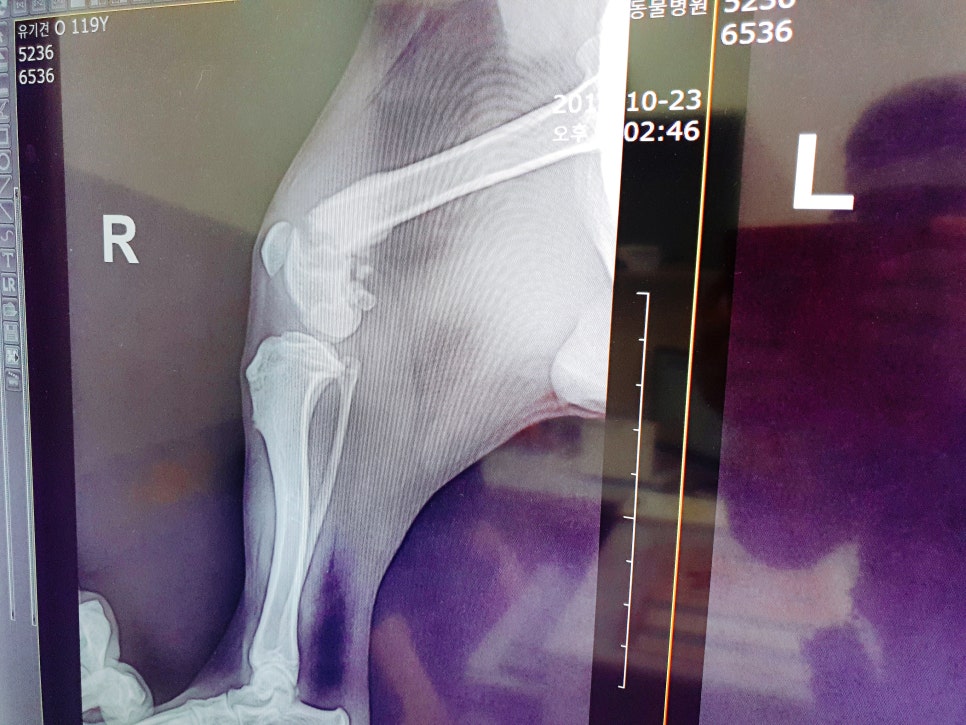

다리 엑스레이를 찍어 보니

아니나 다를까 뒷다리 오른쪽이

골절이 된상태로 적어도

골절후 2주 이상은

지난것 같다고 하더라고요